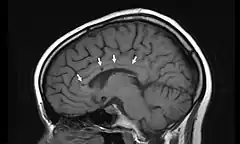

![]() Vista lateral de una resonancia magnética nuclear de la cabeza. Las flechas indican la localización de microinfartos cerebrales característicos del síndrome de Susac. | ||